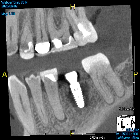

Placed this implant a few weeks ago on healthy patient site #30. Surgery went very smooth, with sequential osteotomies and implant torquing out at 40N/cm. Patient comes back three weeks later and implant is completely spinning with large infection. Brand new set of burs (maybe my second set of osteotomies with that kit) and plenty of water to prevent overheating. Anything I should be thinking about or considering when looking at why these are failing?

**Disclaimer: I have discussed apex of #29 with patient and he is aware of site. Also, I ideally would have seated the implant another 1mm sub-crestal if able to re-do this case. (Oh wait, I will re-do this case!) **

• EDIT: Patient returned today to have implant removed. Removal went fine. But the bigger point is that we found out the issue in this case. Unknown to me, patient is a heavy bruxer had been wearing an orthodontic retainer that was applying significant vertical and lateral force to the implant healing cap. Obviously, this lateral force cause implant instability and most likely is the reason for failure. Frustrating this happened, but happy to know it had nothing to do with my surgical technique!